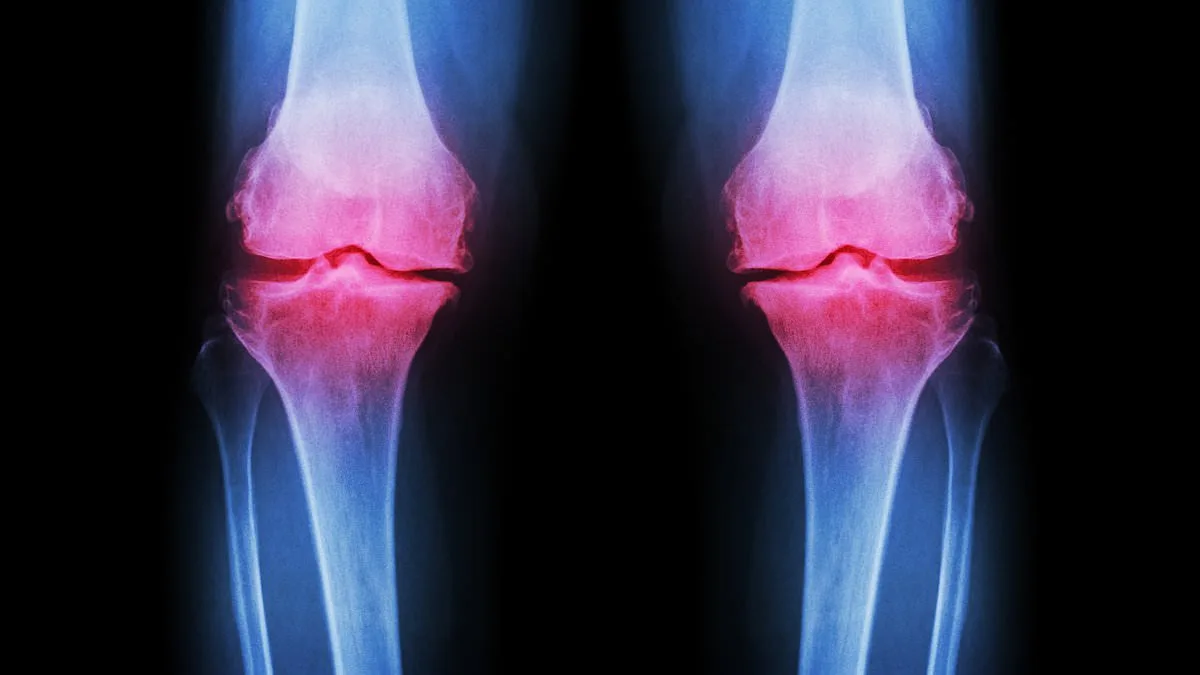

Osteoarthritis occurs when cartilage—the protective tissue between bones—breaks down, causing bones to rub together and joints to swell. Normal joint wear and tear is typically repaired by the body, but excessive strain from repetitive exercise or improper nutrition can overwhelm this process. Post-traumatic osteoarthritis, often linked to fractures in joints like the ankle or knee, is becoming more common among young athletes. 'Improper healing from injuries alters joint mechanics, accelerating cartilage degradation,' explained Sinnett. This condition, which usually appears after 45, is now affecting people as young as 25.